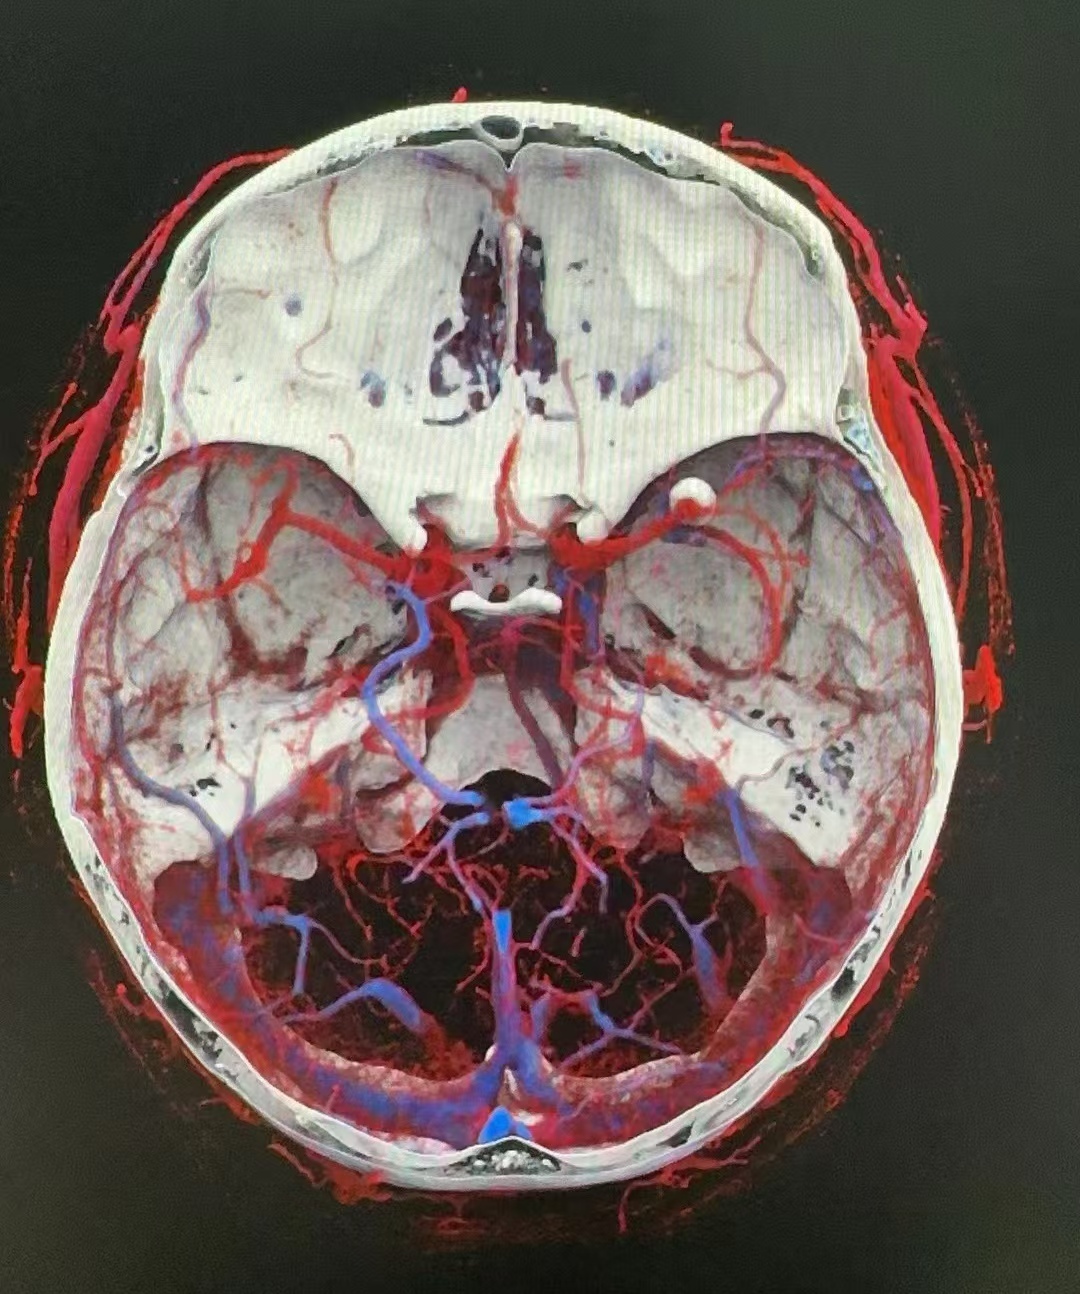

大腦中動脈瘤

治療前檢查發(fā)現(xiàn),但動脈瘤位于大腦中動脈,出血風(fēng)險高,建議治療,微創(chuàng)介入優(yōu)先考慮治療中治療的難點在于下面分支的保護,大腦中動脈瘤的治療我們一共有6種不同的治療策略,我們選擇了支架輔助,關(guān)鍵是術(shù)中彈簧圈的調(diào)整對術(shù)者要求高治療后治療后即刻手術(shù)順利,分支通暢,患者無不適